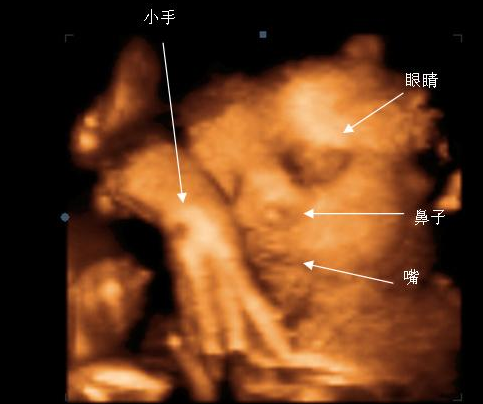

三维彩超表面成像用于产科检查,不仅可观察到胎儿成长的过程,而且可以检查胎盘、羊水及脐带的变化,更重要的是可作为诊断胎儿畸形的主要手段。

美国GE-E8四维数字彩超超越了传统超声的限制,较三维彩超更清晰真实,其出色的人体工程学设计能直观、立体的观察和显示人体器官的动态和三维结构。

准爸妈们通过四维彩超,不仅可以看到宫内胎儿打哈欠、伸懒腰、吮手指等动作,还能够360°观察宫内胎儿的生长发育情况,为早期诊断胎儿先天性体表畸形、先天性心脏疾病提供有效的科学依据。